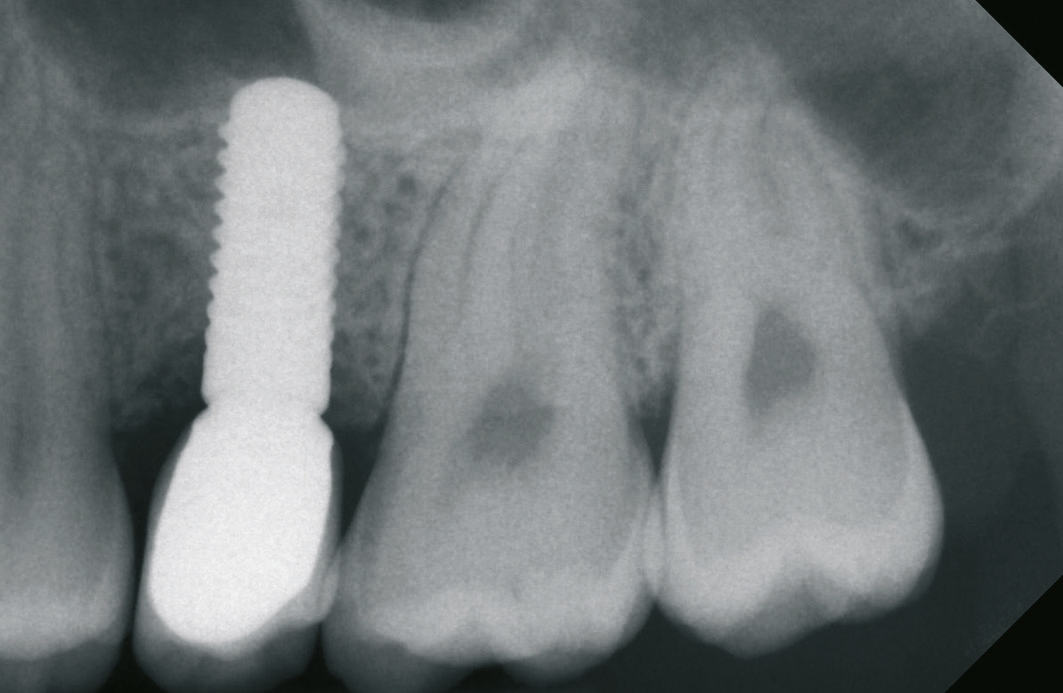

Ein 21-jähriger Patient stellte sich mit einer Perkussionsempfindlichkeit in regio 26 vor. Die klinische Untersuchung zeigte einen tiefzerstörten Zahn 26, dessen gesamte palatinale Wand tief fraktruiert war. Die Frakturgrenze verlief dabei weit unter dem palatinalen Zahnfleischrand (Abb. 1). Nach Erstellung eines Orthopantomogramms und einer radiologischen Einzelzahnbildaufnahme war eine längliche Verschattung am Apex der palatinalen Wurzel des Zahn 26 zu erkennen (Abb. 2), die den Verdacht einer überinstrumentierten Wurzelkanalaufbereitung der palatinalen Wurzel und einer Überstopfung des Füllmaterials bestätigte (Abb. 3). Nach konservierender Theapie wurde die Indikationsstellung für die Extraktion des Zahnes 26 mit einer Sofortimplantation gestellt. Der Periodontal-Screening-Index wies in allen Sextanten Grad 2 auf. Es folgte die Erstellung einer dreidimensionalen Röntgenaufnahme (Orthophos XG 3D, Dentsply Sirona, Bensheim) zur virtuellen Planung der Implantatposition. Die operative Planung erfolgte in der Planungssoftware coDiagnostiX 9.5 (dental wings, Montreal, Kanada) (Abb. 4).

Nach der Präparation des Weichgewebes wurde ein Mukoperiostlappen mit Hilfe der Instrumentenspitze PR2 (Piezosurgery, Mectron, I-Genua) vorsichtig präpariert, um eine suffiziente Deckung der Wunde zu gewährleisten (Abb. 9 und 10). Nach Vorbereitung des Weichgewebes wurde die 3D-gedruckte Bohrschablone auf den Zahnbogen gesetzt und ein Führungsschlüssel mit 2 mm Durchmesser eingesetzt, durch den ein Osteotom einführt wurde, um eine Führung für den nachfolgenden Trepanbohrer in den Knochen kondensierend zu präparieren (Abb. 11). Entlang des Führungskanals wurde das Bett für den allogenen Knochenring (maxgraft bonering; botiss biomaterials GmbH, Berlin) trepaniert (Abb. 12). Der allogene Knochenring wurde extraoral passgenau zugeschnitten und anschließend in die Extrationsalveole platziert (Abb. 13 und 14). Mittels eines breiten Osteotoms wurde der Knochenring samt basalem Knochensegment schablonengestützt nach apikal in den Sinus maxillaris verschoben. Ein parallelwandiges Implantat (Bone Level Roxolid, SLActive, Straumann) mit einem Durchmesser von 4,1 mm und einer Länge von 10 mm wurde zentral in den positionsstabilen Knochenring primärstabil inseriert, mit einer Fixierungkappe (Durchmesser 5,5 mm) versehen und die umliegende Extrationsalveole mit granulärem bovinem Knochenersatzmaterial ausgefüllt (Abb. 15-17). Anschließend wurde die Wunde mit dem Mukoperiostallappen gedeckt und speicheldicht vernäht (Abb. 18). Zur postoperativen Kontrolle wurde ein Orthopantomogramm aufgenommen, auf dem keinerlei Verletzungen benachbarter anatomischer Strukturen zu erkennen sind (Abb. 19). Es folgten zwei radiologische Verlaufskontrollen, vier und sechs Monate nach dem Eingriff, ohne Besonderheiten (Abb. 20 und 21).